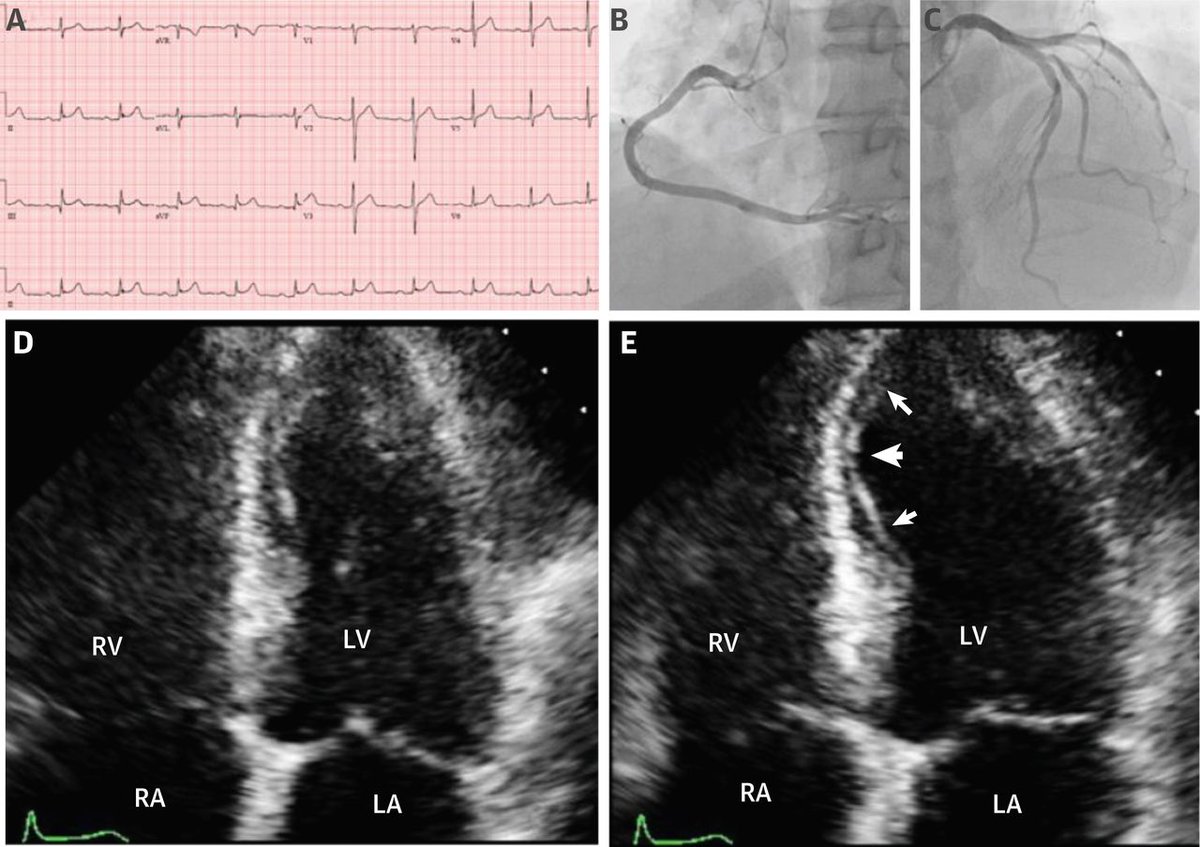

#JACCCaseReports JACC Journals what is this #echogenic structure in the #RV? Let me help: the patient is 29 yrs old male with atypical left sided chest pain and cold fingers and hands Estefania Oliveros MD🫀 Kevin S Shah, MD Edgar Argulian Gina Lundberg MD FACC FAHA Eric Isselbacher Minnow Walsh, MD, MACC David L. Fischman